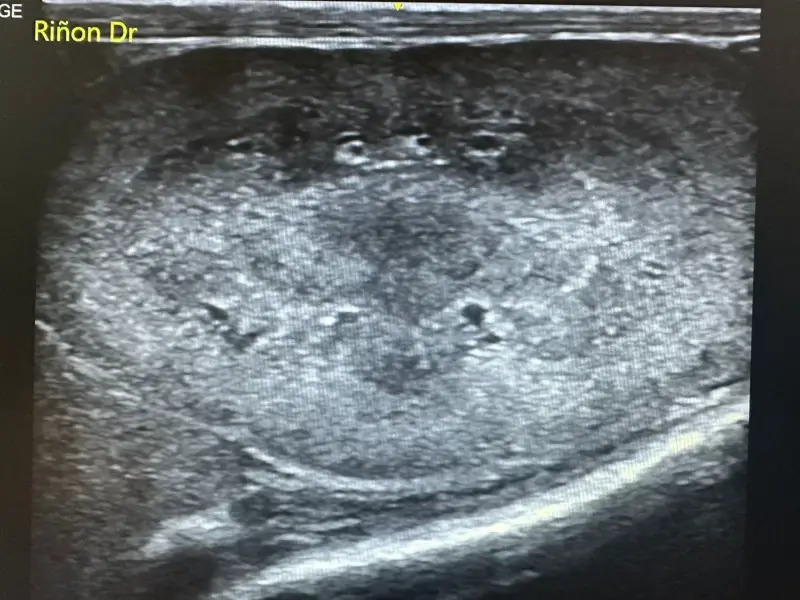

Ecografía abdominal y cardíaca: La ecografía es una técnica no invasiva que permite visualizar órganos internos en tiempo real, evaluando su estructura, tamaño y vascularización. A diferencia de la radiografía, no utiliza radiación y proporciona información sobre la arquitectura interna de los órganos.

Nuestro ecógrafo de alta gama con tecnología doppler color permite:

- Evaluación detallada de riñones, hígado, bazo, páncreas e intestino

La ecografía abdominal es especialmente útil en el diagnóstico de enfermedad renal crónica, permitiendo evaluar el tamaño, la ecogenicidad y la arquitectura renal. Podemos detectar quistes, cálculos renales, hidronefrosis y cambios estructurales indicativos de daño renal antes de que aparezcan síntomas clínicos.